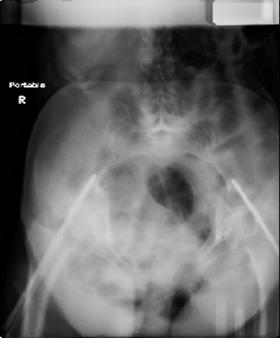

attached are images of a 70 year old female after peds versus car. her own car ran her over.

injuries are limited to the pelvis. left rami open and visible in a 10cm vertical laceration just lateral to left labia majora. wound is grossly clean. no vaginal and no urinary issues. CT scan shows widening of both SI joints anteriorly but I think this is vertically stable pattern.

pt treated that night with I/D and supra-acetabular frame to close the ring. consideration was given for SI screws bilateraly, but given time of night and other factors decision made not to proceed.

so the question is what next operatively if anything? concerns are infection, nonunion anteriorly and possible incompetence of the pelvic floor which may lead to prolapse

issues. right rami are comminuted and plating may entail ilioinguinal approach to extend plate laterally to right iliac wing. retrograde screw up right rami is an option but I am not convinced it will add much. adding SI screws very doable, but major concern is restoring anterior ring. so far wound is clean and closed over a drain, and I have no plans to open it back up and wash again.

maintaining pelvic alignment in ex-fix in 70 yo female for any length of time may be challenging.

any thoughts? would anyone plate the pubic symphysis to close the gap and leave the more lateral rami fractures alone? the most recent pelvic case on this website involved pts with suprapubic catheters and antibiotic options including resorbable beads. I wonder how many people would plate and place antibiotic beads. thanks.